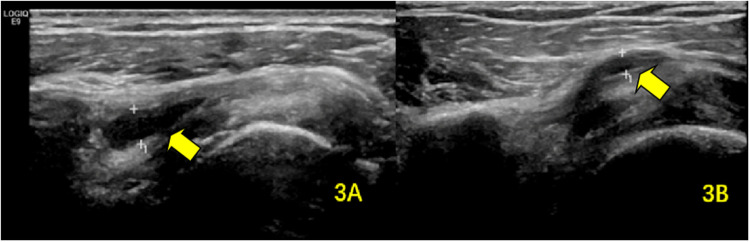

Methods: We conducted a study involving 80 stroke patients with hemiplegia and concomitant shoulder pain on the affected side, admitted to our hospital between April 2020 and March 2021. MSUS was used to evaluate shoulder structures, including the long head of the biceps brachii tendon (BICT) and its sheath, rotator cuff, subacromial-subdeltoid (SA-SD) bursa, labrum, acromioclavicular ligament, acromiocoracoid ligament, and acromion-greater tuberosity (AGT) distance. We compared pre- and post-rehabilitation measurements of supraspinatus tendon (SST) thickness, BICT sheath effusion thickness, SA-SD bursa effusion thickness, AGT distance, and visual analog scale (VAS) scores. Statistical significance was set at P < 0.05.

Results: Post-rehabilitation, the SST thickness on the hemiplegic side showed a statistically significant reduction (P = 0.023). No significant difference was observed in the mean maximum rupture diameter (P = 0.796). Both BICT sheath effusion (P < 0.001) and SA-SD bursa effusion (P < 0.001) exhibited significant decreases. The AGT distance on the hemiplegic side also demonstrated a statistically significant change (P < 0.001). Additionally, the VAS score significantly improved post-rehabilitation (P < 0.001).

Abstract Image